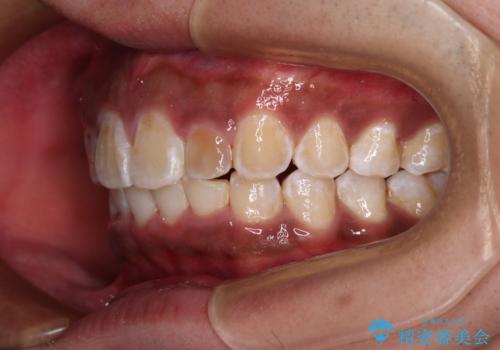

上顎前突とディープバイト ワイヤー矯正での確実に仕上げる

正面や横から見た印象が同じで用であっても、奥歯の咬み合わせが理想的であるかどうかによって、治療の難易度は大きく異なります。

こちらの方も難易度のやや高い状態で、2年以上の期間が予想されましたが、想定通りの2年強で治療を終えることができました。